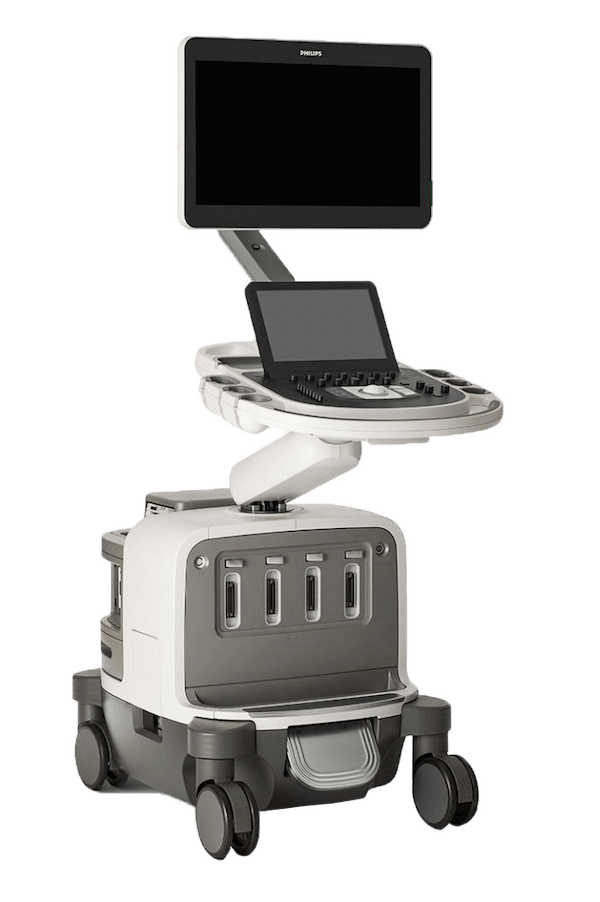

УЗИ аппарат Philips EPIQ Elite

РМК

EPIQ Elite – современная платформа для проведения высокоточных ультразвуковых исследований, разработанная в США специалистами компании Philips Healthcare. Возможность настройки инструментов платформы для осуществления специальных решений, совместимость с широким спектром датчиков, специальные режимы позволяют быстро и точно проводить диагностику даже на начальных стадиях заболеваний.

УЗИ-аппарат Philips EPIQ Elite широко применяют в педиатрии, общей УЗИ-диагностике, хирургии, акушерстве и гинекологии. Но особенно часто он находит применение в кардиологии и при исследованиях сосудов, как и другие аппараты этой линейки. Несмотря на последний факт, EPIQ Elite можно смело считать универсальным диагностическим инструментом для ультразвуковых исследований – он менее успешно помогает медицинским специалистам проводить диагностику в других областях, а специальные возможности упрощают работу медиков и открывают новые горизонты в области УЗИ-диагностики.

- Монитор: 21,5"

- Вес: 104,3 кг

- Активные порты: 4

- Встроенная батарея: Battery

- Высокоплотные датчики: ✔

- Монокристальные датчики: PureWave

- Матричные датчики 2D (двумерные): xMatrix

- CW доплер: ✔

- Тканевой доплер: ✔

- Анатомический М-режим: ✔

- Режим визуализации микро кровотока: MFI

- 3D Freehand: ✔

- 3D/4D: ✔

- Виртуальный источник освещения для получения 3D/4D изображения высокой четкости (по типу HDLive GE): TrueVue

- Объемная динамическая визуализация сердца плода STIC: STIC

- Автоматическое измерение параметров биометрии плода (БПР, ОГ, ОЖ, ДБ) aBiometry: Assist

- Панорамное сканирование: ✔

- Эластография компрессионная: ✔

- Эластография сдвиговая (эластометрия): ✔

- Контрасты для кардиологии: Contrast Card Perfusion

- Контрасты для общих исследований: Contrast GI

- Совмещение данных КТ/МРТ/ПЭТ с УЗИ изображением в реальном времени: PercuNav

- Высокоточная навигация интервенционных инструментов с помощью магнитного поля: PercuNav

- Автоматическое измерение комплекса интима-медиа: IMT

- Автоматические измерение фракции выброса, объемов ЛЖ и других параметров систолической и диастолической функций ЛЖ: a2DQ

- Оценка параметров глобальной и локальной сократимости камер сердца в 2D: aCMQ, SQ

- Стресс эхокардиография: ✔

- Педиатрические датчики: ✔

- Интраоперационные датчики: ✔

- Чреспищеводные датчики: ✔

EPIQ Elite представляет собой УЗИ-аппарат премиум-класса и является отличным образцом современной платформы для ультразвуковых исследований. Широкий выбор режимов сканирования, специальные возможности и функции – вот что делает его популярным среди специалистов в области диагностики.Технология для получения улучшенного изображения XRES Pro

Особенности аппарата УЗИ Philips EPIQ Elite

Платформа оснащена большим монитором с диагональю 24 дюйма и повышенной яркостью, а также с возможностью изменения положения экрана для улучшения качества обзора.